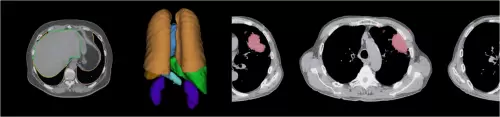

富士胶片的人工智能技术REiLI,来源于最先进的人工智能技术与我们传统优势的图像处理技术的结合。富士胶片计划凭借REiLI实现未来诊断流程。在成像检查后,REiLI将能识别器官的形状,并发现与正常组织结构不同的部分,针对检测到的特征,它会根据疾病和人体部位对患者进行分类,并向相应领域中最适合的放射科医师发出通知。放射科医师收到提醒后开始阅读研究报告,给检测到的特征做注释以便于识别。REiLI还能根据数据库列出患者潜在的疾病状况,以便放射科医师能够有效地进行诊断。